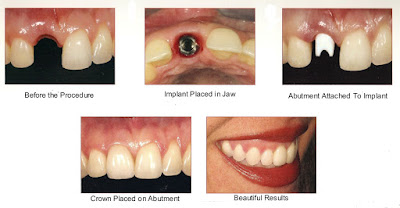

Secara umum pemasangan implan gigi dilakukan 2-2.5 bulan setelah pencabutan gigi, dimaksudkan karena luka pada tulang bekas pencabutan gigi telah sembuh dan tulang baru yang sehat telah terbentuk sehingga dental implant akan dapat dipasang dengan baik. Hal ini dimaksudkan, dental implant dapat terpasang dengan baik di tulang dan dapat diperoleh primary stability, yaitu terpasangnya dental implant secara kencang pada tulang rahang di awal pemasangan. Primary stability diperlukan agar proses penyatuan antara dental implant dengan tulang rahang melalui proses yang disebut dengan osseointegration.dapat berlangsung dan proses ini akan berjalan dalam kurun waktu antara 2-2.5 bulan setelah dental implant terpasang. Setelah dental implant mengalami osseointegrasi, tahapan selanjutnya adalah pemasangan mahkota gigi yang didahului dengan pemasangan bagian di atas dental implant yang disebut dengan abutment implant.

(catatan: terjadinya osseointegrasi dental implant dan tulang disekitarnya merupakan penentu keberhasilan pemasangan suatu implan gigi)